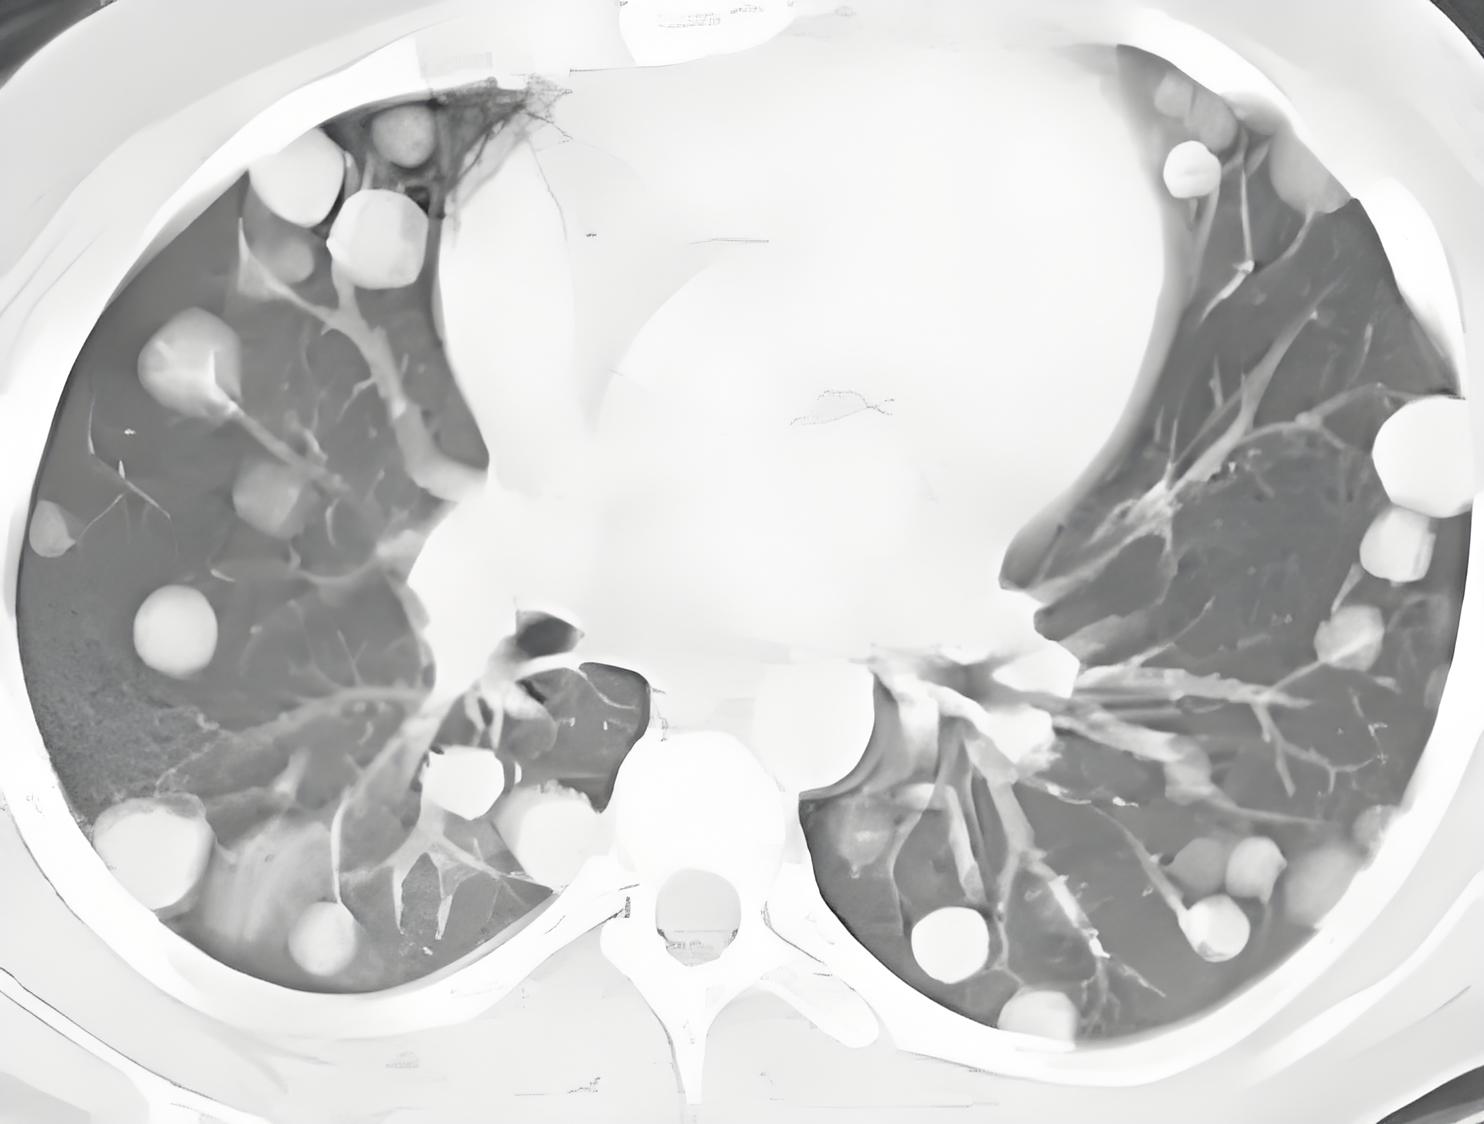

面对晚期癌症,治疗决策需要权衡多方因素。上周,我为一位晚期肺癌患者制定了三种方案:

维度一:疾病特点

癌症类型(小细胞癌vs非小细胞癌)

分子特征(EGFR/ALK等基因状态)

转移部位(骨转移vs脑转移)

以晚期非小细胞肺癌为例:

方案A(积极治疗)

PD-1抑制剂+化疗+中医药

中位生存期:18-24个月

年费用:医保后约5-8万

副作用:可能免疫性肺炎、甲减

方案B(温和治疗)

单药靶向+中医药治疗(如有敏感突变)

中位生存期:12-36个月(因药而异)

年费用:医保后1-3万

副作用:皮疹、腹泻

方案C(最佳支持治疗)

中医药+止痛、营养支持

中位生存期:4-6个月

聚焦生活质量